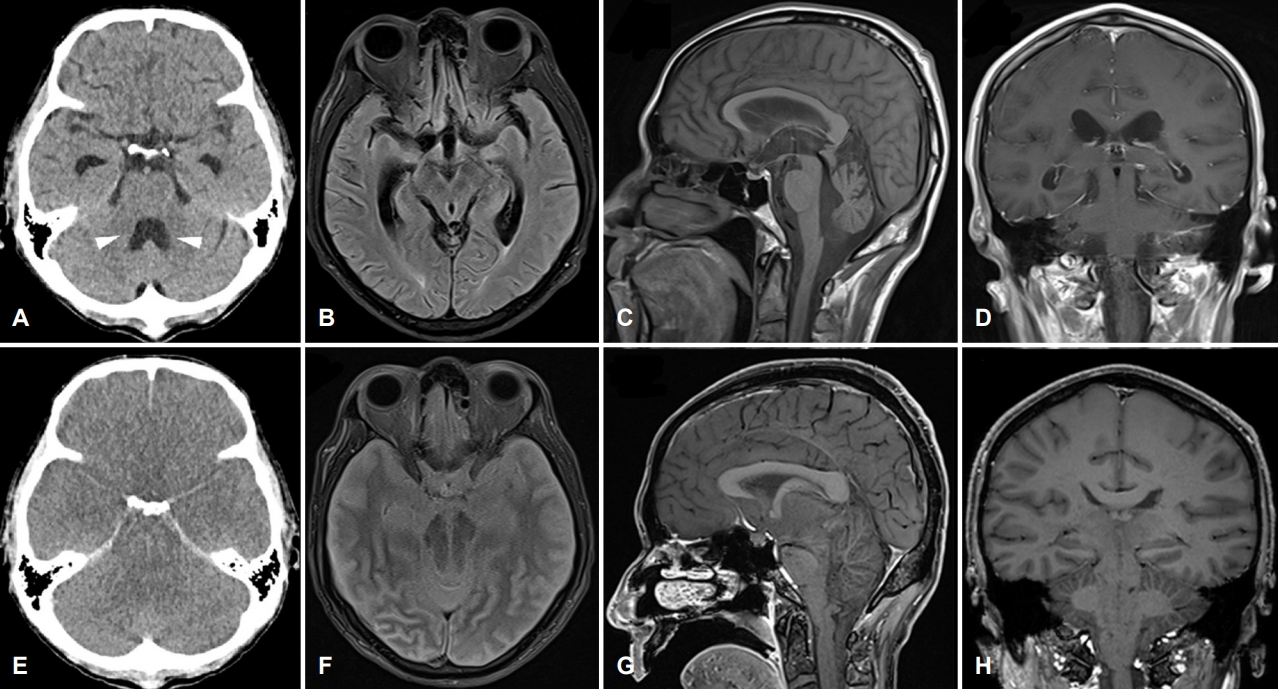

진행성 위암 및 췌장 전이로 항암 치료를 받았던 59세 남자로 최근 식욕 부진, 구역, 두통을 호소하던 중, 7일 전부터 급격히 진행하는 청력저하로 뇌 자기공명영상을 시행하였으나 뇌전이 또는 암종수막염(carcinomatous meningitis)을 시사하는 소견은 관찰되지 않았다. 내원 4일 전부터 시력저하, 3일 전부터 의식저하가 발생하여 응급실에 내원하였고, 호흡부전이 동반되어 있어 기관내삽관을 진행하였다. 응급실에서 시행한 뇌 computed tomography (CT)에서 경도의 뇌실 확장이 의심되는 소견 외에 급격한 뇌압 상승 등 의식장애의 원인은 관찰되지 않았다(Fig. A-D). 초기 신경계진찰에서 의식은 혼수이나 뇌간반사는 유지되었다. 입원 당일 의식장애의 원인을 감별하기 위해 시행한 요추천자 시 분출되어 쏟아지는 양상의 높은 뇌척수압이 관찰되어 검사를 중단하였다. 요추천자 시행 1시간 뒤, 적절히 유지되던 혈압이 64/42로 저하되고, 환자의 자발호흡이 소실되었다. 신경계진찰에서 양쪽 동공이 확대 고정되고, 전정안반사, 각막반사가 소실되었다. 12시간 뒤 시행한 뇌 자기공명영상에서 미만성 대뇌부종 및 허탈된 뇌실(collapsed ventricle), 간뇌와 중뇌의 부종과 중심탈출(central herniation), 전반적인 소뇌부종과 편도탈출(tonsillar herniation) 등이 확인되었다(Fig. F-H). 만니톨 및 11.7% 고장성 식염수를 주입하였으나 호전되지 않았다. 2일 뒤 시행한 뇌 CT에서 미만성 뇌부종 및 중심탈출이 진행하는 양상이 관찰되었다(Fig. E). 요추천자 10일 후 환자는 사망하였다.

본 증례 영상의 특징적인 소견은 대뇌 부종의 정도에 비해 심한 뇌실의 허탈이 관찰되는 것과 간뇌(diencephalon)와 중뇌가 소뇌천막 주변에서 심한 부종을 보이는 점이다. 이는 요추천자 당시 빠르게 배액된 뇌척수액으로 인해 급격한 대뇌의 하방전이(shifting)가 발생하고, 이로 인해 순간적으로 간뇌와 중뇌가 천막패임(tentorial notch)의 좁은 공간으로 비집고 들어가면서 압박을 받아 부종이 발생한 것으로 판단된다.